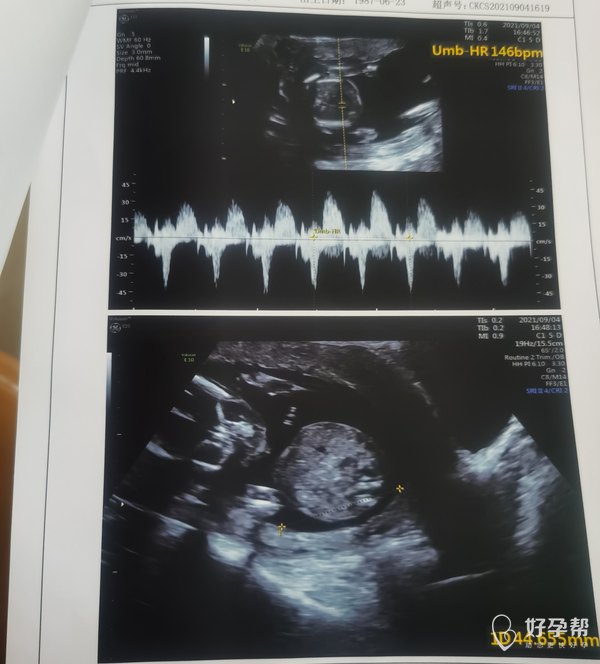

请医生帮我看一下:1、我有没有羊水过多?2、我的胎盘是不是离宫颈口较远(之前是描述距离近),不用担心胎盘低置问题了?3、我的子宫是左旋子宫还是右旋呢,我应该靠左侧睡还是右侧睡更好?仰睡真的会影响宝宝 可能导致缺氧么?4、宝宝的股骨是不是偏小?需要加强补钙么?目前我每天吃一颗醋酸钙。5、我之前的B超都是头位 现在变成臀位了,请问后面是不是还会变化?

羊水量正常,胎盘位置可以的,不是低置,胎盘在后壁不要仰卧睡,一般左侧睡。股骨现在还太小,正常发育就可以的,可以补钙的,头位臀位现在可以变化的。